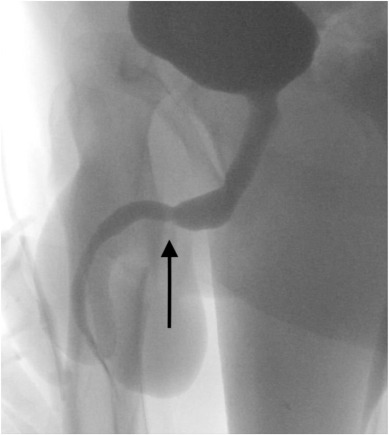

Um fluoroscópico uretrograma foi organizado duas semanas após o procedimento para avaliar a cicatrização uretral antes da remoção dos cateteres. Nenhuma evidência de vazamento de urina ou estenose uretral foi observada, exceto uma leve mudança de calibre na bulbar distal e na uretra peniana proximal, na posição da uretrostomia recente.